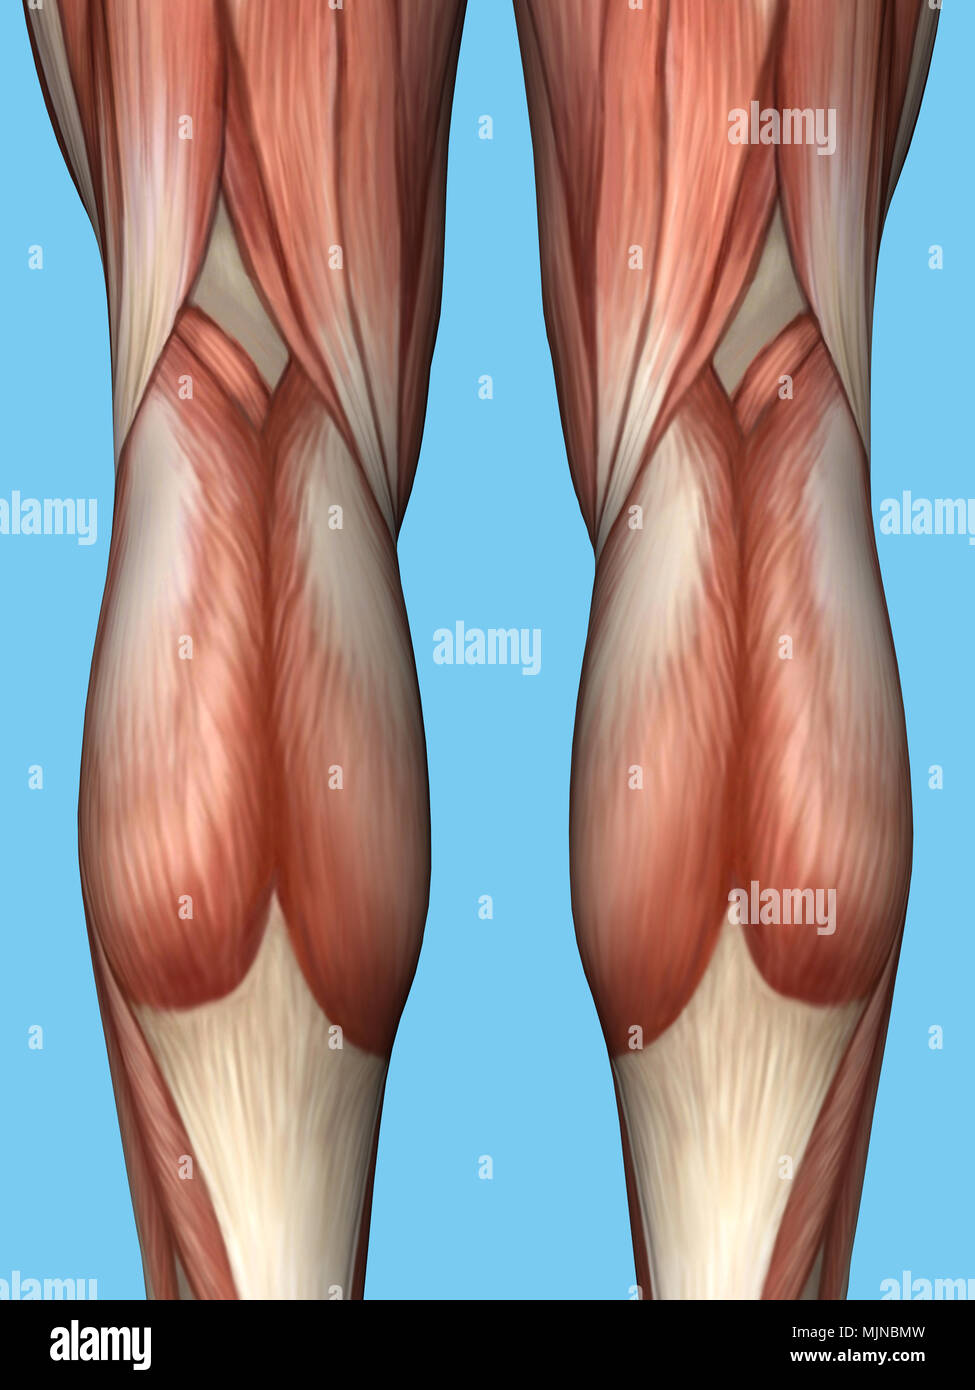

Anatomie de l'arrière de la jambe. Banque D'Imageshttps://www.alamyimages.fr/image-license-details/?v=1https://www.alamyimages.fr/anatomie-de-l-arriere-de-la-jambe-image183637689.html

Anatomie de l'arrière de la jambe. Banque D'Imageshttps://www.alamyimages.fr/image-license-details/?v=1https://www.alamyimages.fr/anatomie-de-l-arriere-de-la-jambe-image183637689.htmlRMMJNBMW–Anatomie de l'arrière de la jambe.